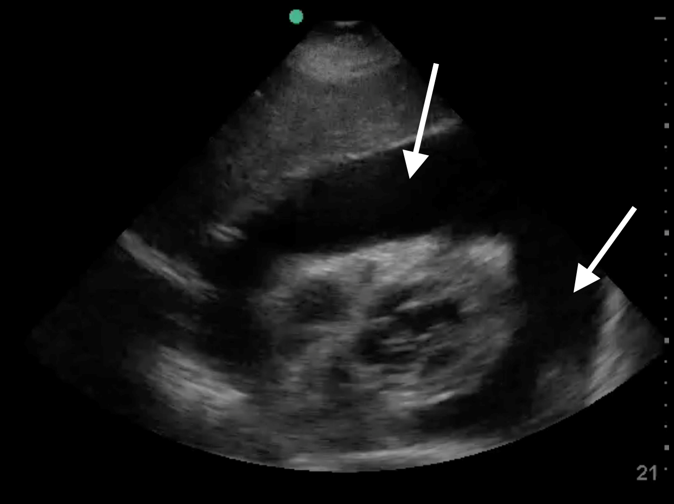

RUSH Pericardial Fluid Subxiphoid View Image

Arrows: Pericardial Fluid (Effusion)